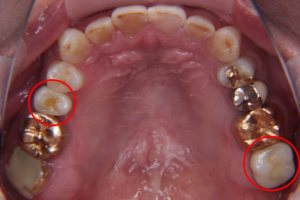

こちらが治療前のレントゲン写真です。丸を付けた箇所がインプラント治療を受ける場所です。

左の赤丸は、虫歯の為、歯の根っこが悪くなり抜歯が必要な場所です。(右上4番)

右の赤丸は、歯が抜けたまま放置されていた場所です。(左上7番)

治療後の全体の写真とレントゲン写真がこちらです。